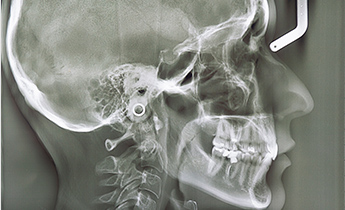

セファロは、口腔内の状態を検査するために撮影するレントゲンの一種で、頭部X線規格写真とも呼ばれます。セファロの検査情報は、矯正治療においても欠かせない情報で、顎骨の成長状態や歯の位置関係、噛み合わせ、顔全体のバランスなどを確認するために用います。

正しく矯正治療を行うためには、歯並びだけでなくお顔全体の骨格なども詳細に把握する必要があります。そこで、当院では口腔内スキャナー(トリオス)やセファロを用いた精密な検査を行い、患者様の口腔内の3次元情報を詳細に把握します。